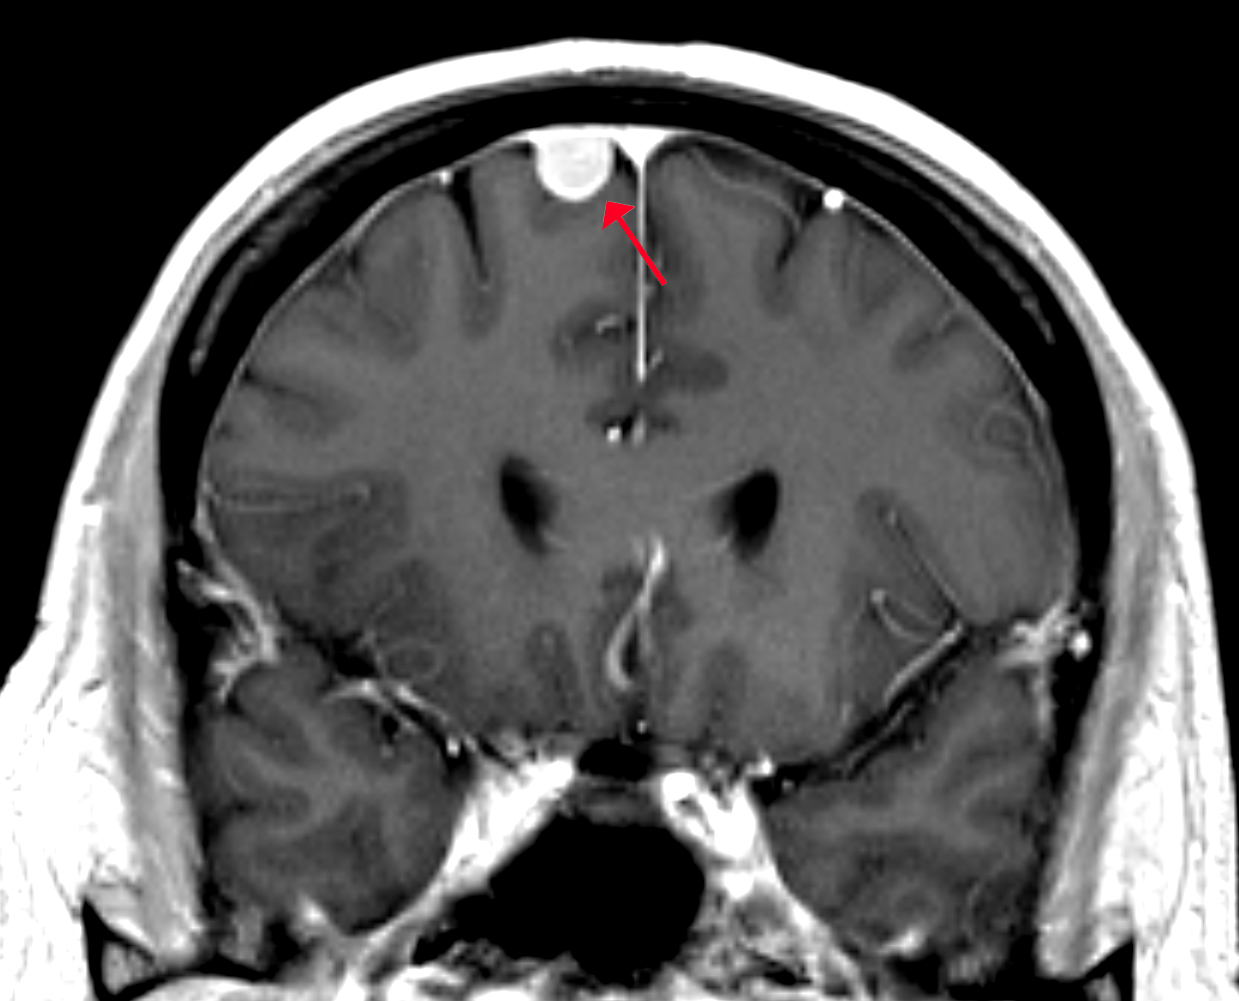

增強磁共振圖像

圖像所見:

顱腦磁共振增強掃描,于腦內右側額部見一枚類圓形明顯均勻強化占位性病變,大小約0.85X1.18X1.42cm,邊界清楚,信號均勻,病灶呈寬基底,于顱骨內板相連,臨近腦回受壓推移,周圍腦溝增寬,可見腦膜尾征。雙側側腦室旁,余腦實質內未見明顯異常。

印象:右側額葉占位性病變,考慮腦膜瘤。